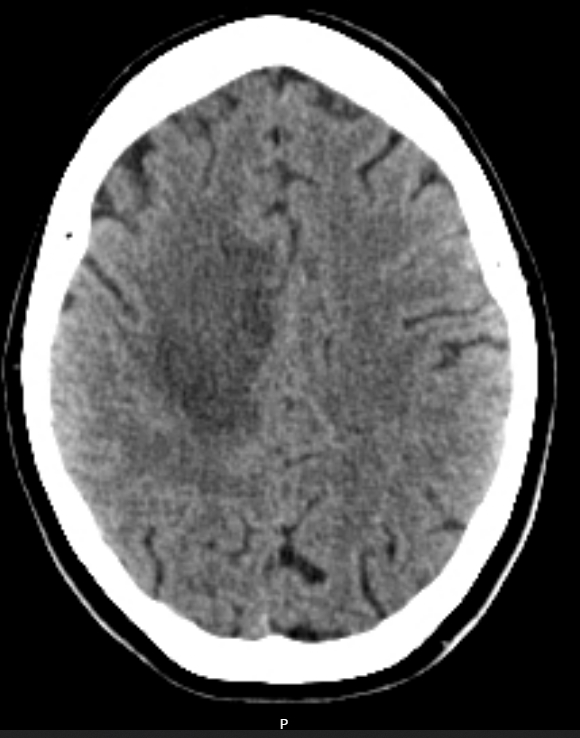

A CT-Brain is urgently booked 2 days later. (Click to open images)

Describe these CT images

Axial slices

Large hypodense space-occupying lesion in the right frontal/pareital lobe

Poorly defined borders

Midline sulcal effacement and minor midline shift

No ventricular obstruction

No obvious signs of raised ICP